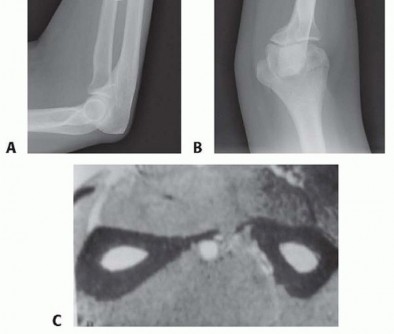

FIG 3 • A,B. AP and lateral radiographs demonstrate a segmental radius shaft fracture resulting in a malunion both proximally and distally despite open reduction and internal fixation. Note the loss of radial bow in both direction and magnitude, narrowing of the interosseous space between the radius and ulna, dorsal positioning of the distal ulna, and nonunion of the basilar ulnar styloid fracture. The patient was unable to supinate to neutral and demonstrated instability at the DRUJ. C. CT scan demonstrates narrowing of the interosseous space with heterotopic bone formation. P.219The degree of angulation and comminution can be calculated from these films.Contralateral forearm films provide a comparison for the amount of shortening as well as for the location and angle of the radial bow. 9A computed tomography (CT) ( FIG 3C) scan or magnetic resonance imaging (MRI) can also be obtained to assess for malrotation.2